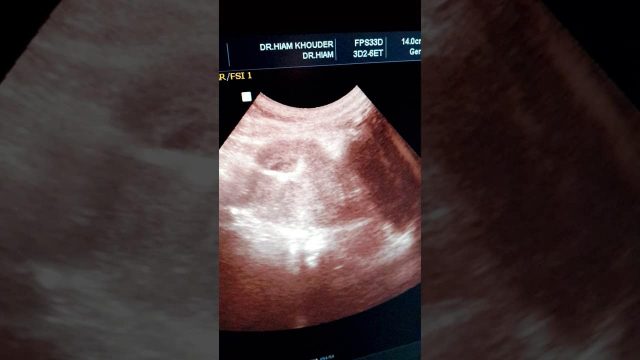

“هل يمكن لي أن أحمل مع وجود اللولب؟” سؤال كثيرا ما تطرحه العديد من السيدات على أنفسهن أو الطبيب المباشر، أما عن الإجابة عنه فنعم؛ حيث كشفت الدراسات أن جميع الوسائل المستخدمة لمنع الحمل، هي وسائل لا يمكن لها أن تؤدي هذه الوظيفة بشكل قطعي ونهائي مهما بلغت درجة فعاليتها، وذلك لأسباب واعتبارات كثيرة ومتنوعة. ولا يعد اللولب استثناء في هذا الشأن، ولكنه يظل دائما من الخيارات الهامة والمفيدة.

إذا كنت من اللواتي يستخدمن تقنية اللولب ولاحظت نزول بقع من الدم منك، فهذه إشارة قوية على أنك حامل سيدتي. ويحدث النزيف عادةً عند غرس البويضة الملقّحة في جدار الرّحم، حينها تعاني المرأة أيضا من حدوث انقباضات مشابهة لتلك التي تصاحب نزول الحيض، ولكن بصفة أقل حدّة. (Treerush.com)

بصفة عامة، يشكل الحمل مع اللولب خطرا على صحة المرأة وجنينها، ومن أجل ذلك يتوجب عليها الاتوجه فورا إلى الطيب بمجرد ملاحظتها للنزيف، بالإضافة إلى الأعراض التالية :